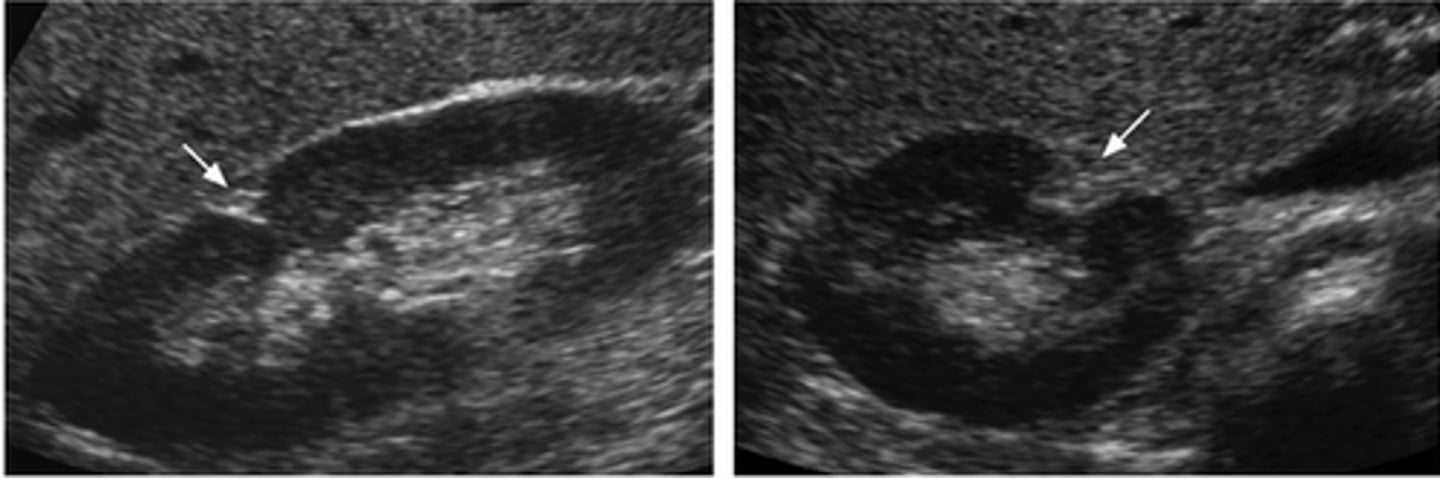

What normal variant of the kidney may mimic a renal mass or duplicated urinary system?

Hypertrophied Column of Bertin

Prominent folds of renal cortical tissue that protrude down into the medulla towards the renal sinus

Clearly separated from the renal sinus

Continguous with renal cortex

Echogenicity is the same as the cortex/renal parenchyma

Not over 3 cm in size as a rule